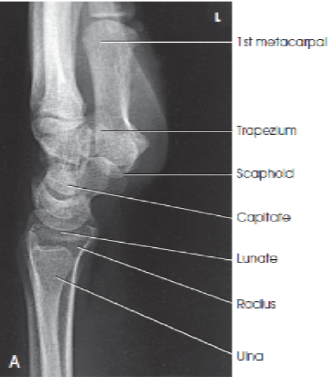

What are the structures shown in a lateral wrist image

A

distal radius and ulna, carpals, and proximal half of metacarpals

What is the evaluation criteria for a lateral wrist?

superimposed distal radius and ulna

superimposed metacarpals

bony trabecular detail and surrounding soft tissues